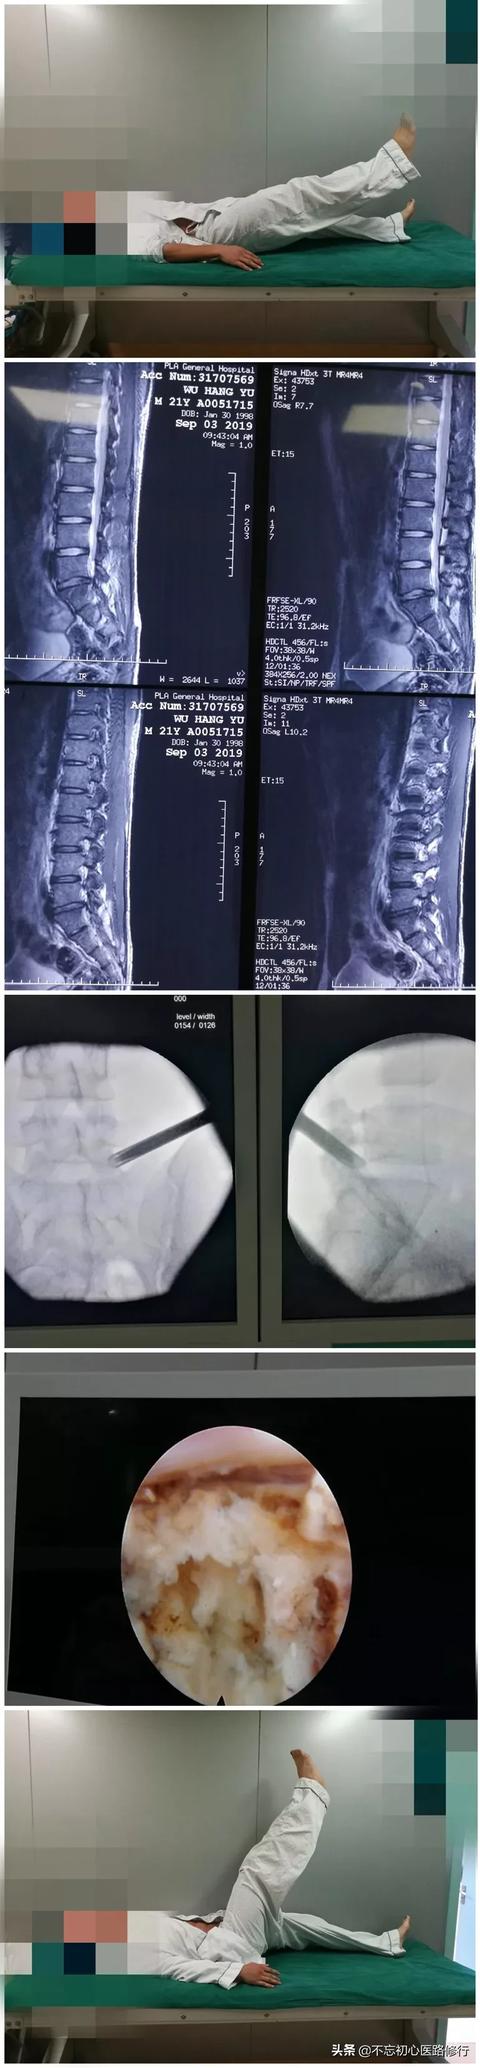

Avant de répondre à la question du taux de réussite de la chirurgie, nous devons être clairs sur deux points : premièrement, notre diagnostic doit être correct, c'est-à-dire que les symptômes cliniques et l'imagerie doivent correspondre ; deuxièmement, la douleur doit être causée par une hernie discale lombaire et non par une pathologie des tissus mous telle qu'une lésion myofasciale.

On pense actuellement que la hernie discale lombaire provoque des douleurs lombaires par deux mécanismes, l'un étant le mécanisme de compression, c'est-à-dire que le noyau pulpeux saillant du disque intervertébral comprime directement la racine du nerf rachidien, et l'autre étant le mécanisme à médiation inflammatoire, qui est causé par la rupture de l'anneau fibreux, le noyau pulpeux saillant du disque intervertébral libère des médiateurs inflammatoires et stimule la racine du nerf rachidien pour provoquer la douleur.

La chirurgie de la hernie discale lombaire se divise aujourd'hui en deux catégories : la chirurgie mini-invasive et la chirurgie ouverte. Les deux premiers types de chirurgie sont davantage pratiqués dans le service de la douleur, ce qui est moins traumatisant et permet une guérison plus rapide, mais uniquement pour les petits cas de hernie discale et, d'après l'expérience passée, l'effet de soulagement de la douleur est encore très bon au moment de l'apparition de la douleur aiguë.

L'incision de la chirurgie du diamètre du foramen intervertébral est petite, généralement d'environ 7 mm, sans détruire les muscles et les ligaments paravertébraux, avec moins de saignements, sans effet sur la stabilité de la colonne vertébrale, et le symptôme de la douleur est soulagé rapidement grâce à l'élimination de la compression nerveuse après l'opération. La chirurgie ouverte s'adresse aux patients présentant une hernie discale lombaire accompagnée d'une dégénérescence vertébrale lombaire, d'ostéophytes, d'une sténose spinale et d'une sténose du canal de la racine nerveuse, d'une calcification ligamentaire, ainsi qu'aux patients présentant une instabilité évidente de la colonne vertébrale lombaire.

Si les indications sont bien choisies, le taux de réussite de la procédure peut atteindre 90 ou 95 %, voire plus. Si les indications ne sont pas correctement choisies, le taux de réussite se situera essentiellement autour de 60 %. Les indications spécifiques de l'intervention chirurgicale sont les suivantes : le patient présente d'abord des douleurs lombaires, des fourmillements dans les deux membres inférieurs, un test positif d'élévation de la jambe droite, une réduction significative de la force des dorsiflexeurs du pouce des deux pieds et une limitation significative des activités lombaires fonctionnelles du patient.